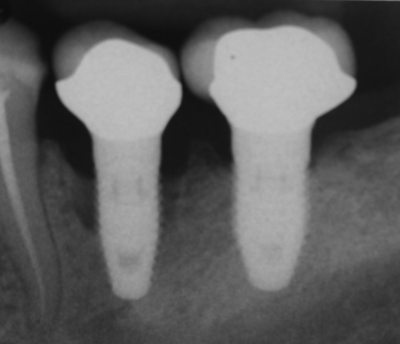

Deep Dive: Updated Guidelines on Implant Placement and Medication-Related Osteonecrosis of the Jaw (MRONJ)

As an oral surgeon, I’m seeing more patients than ever on antiresorptive medications, primarily for osteoporosis or cancer-related bone conditions. In Canada alone, over 2 million people are affected by osteoporosis, with many receiving bone-sparing therapies such as bisphosphonates and denosumab (CMAJ). This prevalence underscores the importance of understanding